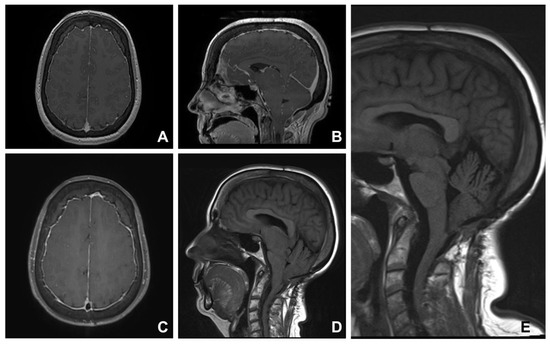

3.4. Group Four. Idiopathic Intracranial Hypertension

| 11 | 26 | F | Occipital headache Visual disturbance | 5 | Empty sella, CSF around optic nerves | Surgical decompression Ventriculoperitoneal shunt insertion | Improved |

| 12 | 30 | F | Occipital headache | 8 | Tortuosity of optic nerve | Medical management | Not applicable |